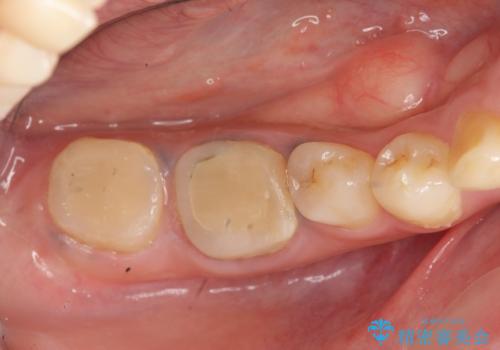

- 治療途中の奥歯の治療の続きを希望され、来院されました。

治療途中で長期間放置していたため、歯が歯ぐきから挺出(伸びてくる)してしまい、十分に強度を担保できるセラミッククラウンを装着するスペースが不足した状態です。